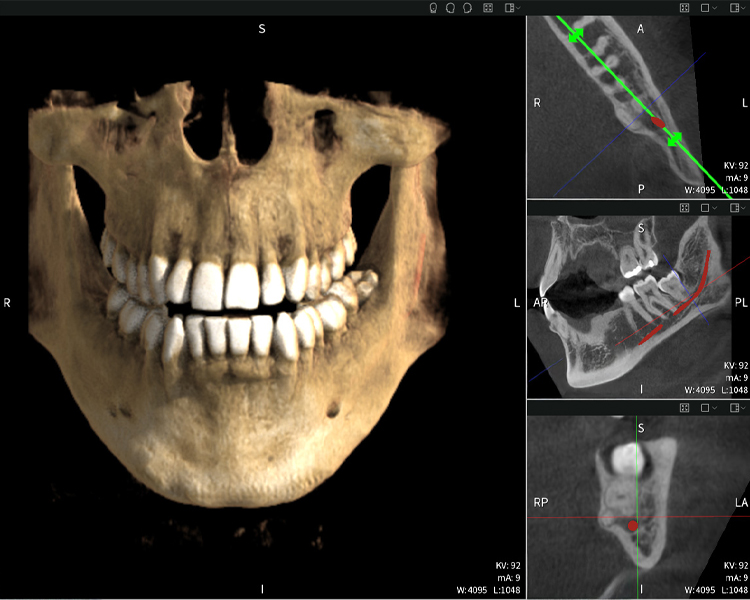

Figura d: Resultados de imagen de Seethrough Max, sobre un fondo negro.

Figura d

Las figuras b–d muestran varias vistas de una reconstrucción 3D de la mandíbula, proporcionando una visión general completa de la anatomía mandibular, la posición de los nervios en relación con los dientes y permitiendo evaluar la simetría y alineación dentaria.

La figura d muestra el diente 48 previamente tratado, con la corona retirada y las raíces dejadas en proximidad al nervio, lo que ilustra el alto riesgo de daño nervioso.